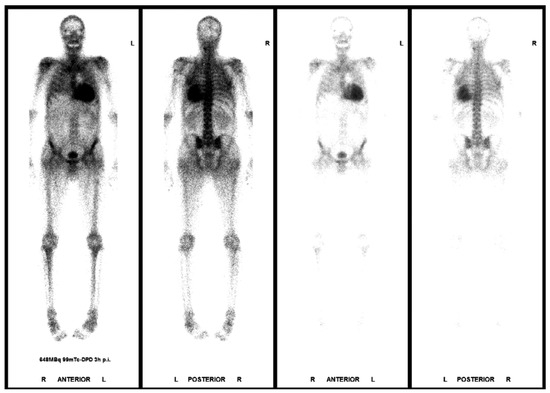

The Eustachian ridge is ablated as part of the cavotricuspid isthmus (CTI) involved in typical atrial flutter (AFL) ablation, but is itself rarely an arrhythmogenic focus. We report a case of a patient with dual tachycardia involving the CTI area....